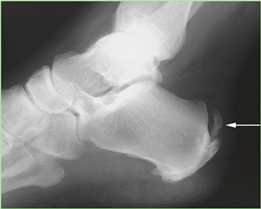

Conversely, hallux rigidus represents a degenerative cascade characterized by osteophyte formation, dorsal impingement, and progressive loss of sagittal plane motion at the first MTP joint. While trauma and inflammatory arthropathies can precipitate this condition, the most common etiology is idiopathic, often linked to an elevated or elongated first metatarsal (metatarsus primus elevatus), which alters the joint's instant center of rotation and accelerates articular wear. Recognizing these distinct pathophysiological pathways is paramount for the orthopedic surgeon, as it dictates the selection of joint-sparing osteotomies versus joint-sacrificing arthrodesis.

Weight-bearing anteroposterior (AP), lateral, and sesamoid axial radiographs are mandatory. On the AP view, the surgeon measures the Hallux Valgus Angle (HVA, normal < 15°), the Intermetatarsal Angle (IMA, normal < 9°), and the Distal Metatarsal Articular Angle (DMAA). The lateral view is scrutinized for Meary's angle (talo-first metatarsal angle) to identify midfoot collapse, as well as the presence of dorsal osteophytes indicative of hallux rigidus. The sesamoid axial view is critical for assessing the degree of sesamoid subluxation and the integrity of the crista.